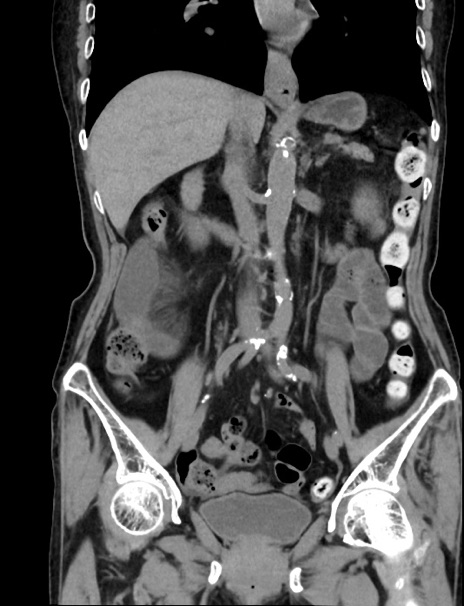

症例33(冠状断像)

【症例】70歳代 女性

【主訴】心窩部痛

【現病歴】延髄病変の精査・加療にて神経内科入院中。本日より心窩部痛あり。

【既往歴】虫垂炎

【身体所見】右下腹部を中心に圧痛と反跳痛あり。

【データ】WBC 10900、CRP 0.02